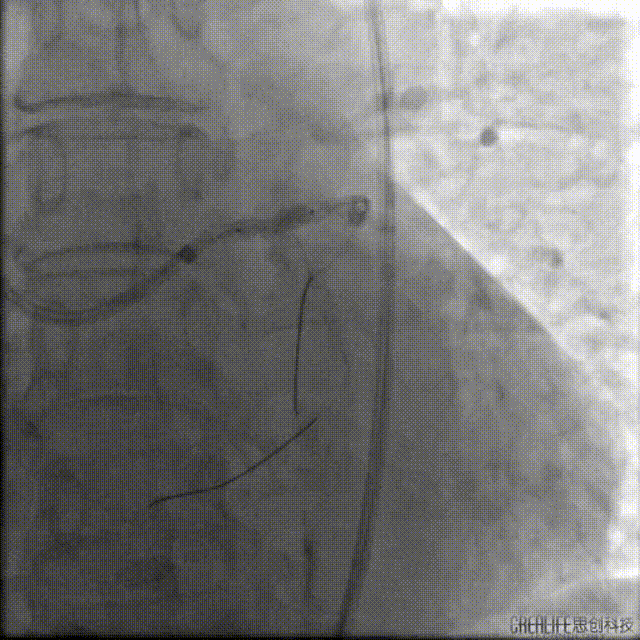

主干末端POT,提示支架内膨胀不全(偏心,下图一蜘蛛位扩张满意,下图二肝位扩张不全,下图三肝位复查造影提示支架膨胀不全)。

此时要选择腔内影像指导?但超选已明确为支架膨胀不良。虽为主干支架,但目前左冠血流TIMI-III级,已达急诊目的,拟充分抗栓下选择Shockwave血管内冲击波导管处理。